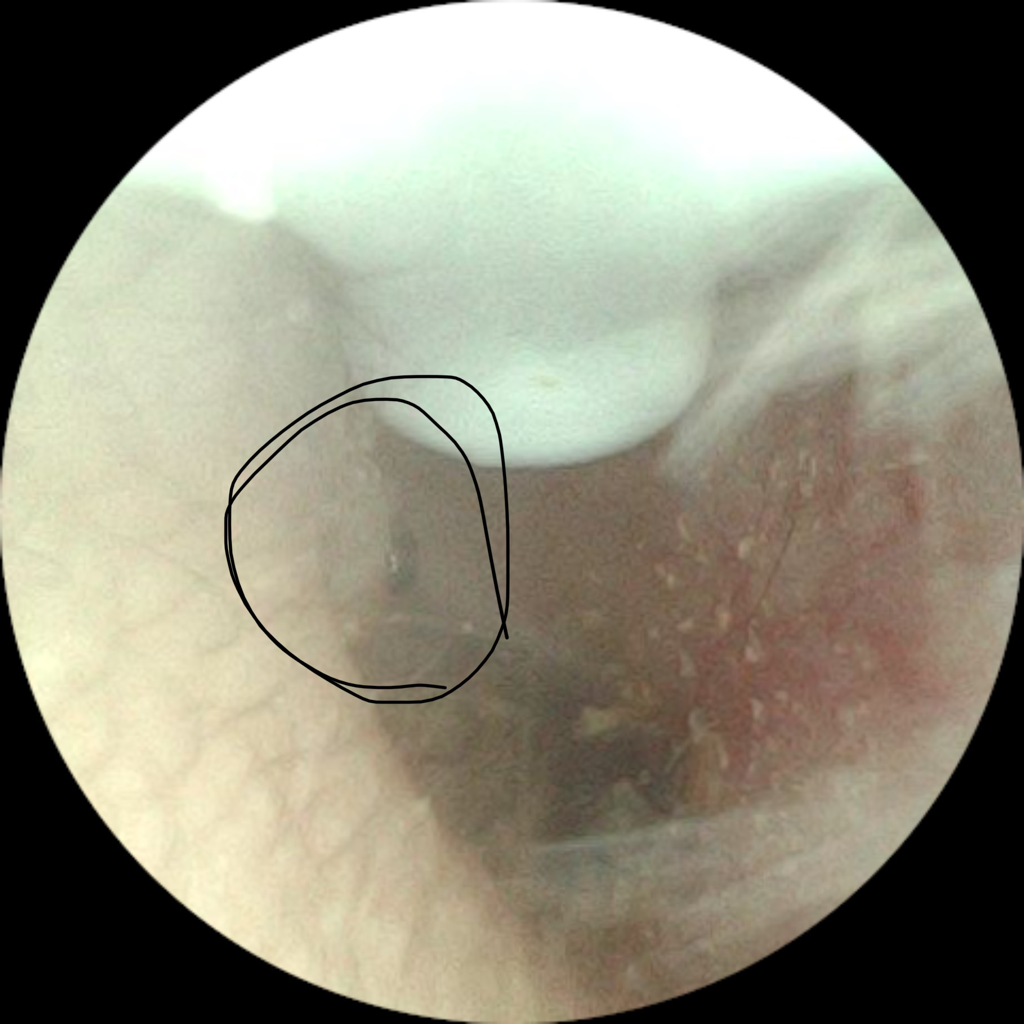

귀 안에서 검은 점 이거 뭔가요?

귀파다가 발견했는데 이거 뭔가요? 점은 아닌거같은데

건들면 살짝 아프긴해요 ㅜㅠㅠ

이빈후과 가봐야할까요? 궁금합니다!!!

사진이 흐려 정확히는 알 수 없겠으나 이전에 귀를 파면서 생긴 외상으로 인한 딱지일 가능성이 있으며, 통증이 심하다면 염증으로 발전할 수 있으므로 이비인후과에 가셔서 진료를 보시는 것이 도움이 될 것으로 사료됩니다.